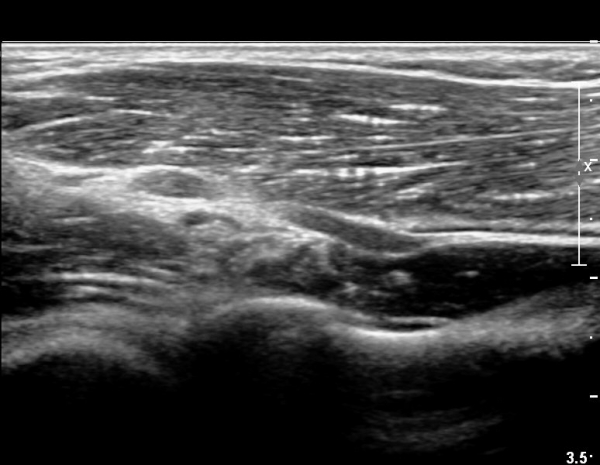

ŽÃËÀÚ¸¦ ¸»´ÜÀ¸·Î Á¶±Ý À̵¿ÇÏ´Ï Èİñ°£ ½Å°æÀÌ ÀÛ¾ÆÁö°í(»çÁø 2),